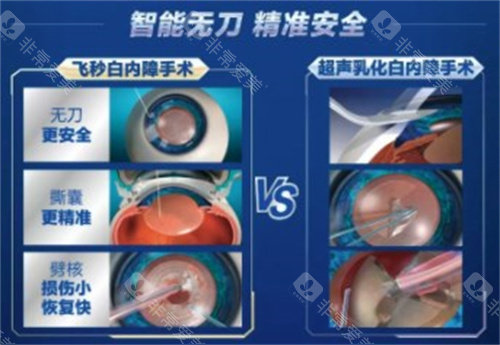

白内障正规开展了多种白内障手术,包括超声乳化白内障吸除术等,手术技术成熟,术后结果良好。

此外,科室还开展了一些潮流的眼科手术技术,如飞秒激光辅助白内障手术等,大大提高了手术的可靠性和有效性。